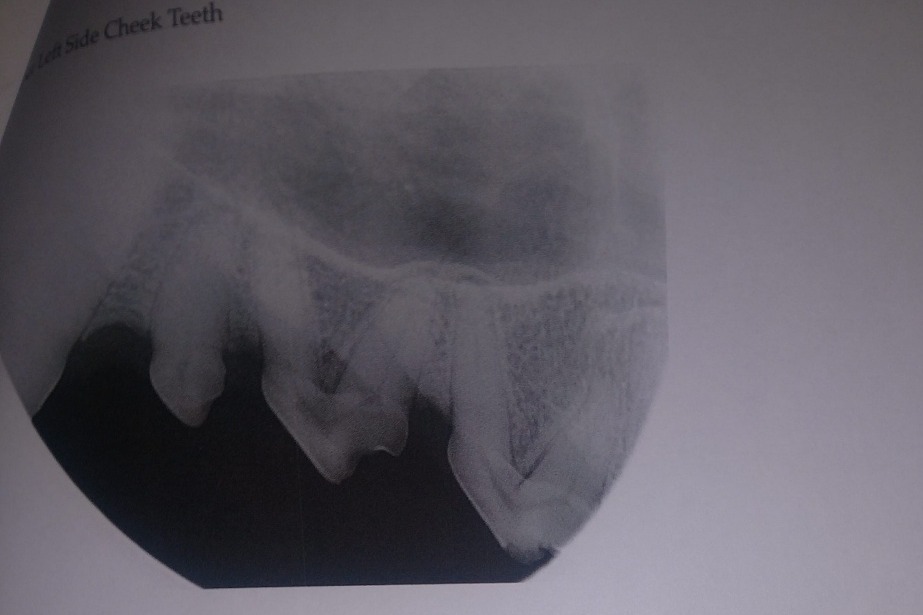

The following photos are her radiographs for anyone that knows how to read them, so you can see all the dead teeth that need future extractions, and some show the root canals:

The radiographs laid out a dim story of that long term damage: all 4 canine teeth were dead, 2 of those canines were broken off from the recent attempt on the gate; all of her lower incisors, and several molars on each side were also dead. The vet was surprised, in spite of massively evident wear and tear, that her upper incisors appeared to still be alive. More of her teeth were dead than live. However, there was some good news in that her gums were completely free of gum disease, she had very little plaque and tartar buildup, and that she hadn't lost any of the bone her teeth were seated in.

AFTER PHOTOS: (left upper and lower canine root canals, cleaning)